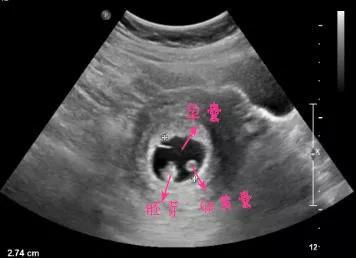

怀孕早期的B超检查主要是为了排除异位妊娠和异常妊娠,确定宝宝在妈妈的子宫里安全存活了。这时候的B超单上主要会出现妊娠囊(孕囊)、卵黄囊、胚芽、胎心这些指标。

正常情况下,如果子宫内出现孕囊,孕囊里有卵黄囊、胎芽及胎心,就基本可以确定宝宝安全了。如果没有观测到其中的某些指标也不要过于担心。可能是你太心急了,一般怀孕5~6周可以看孕囊,6~7周的时候可以看到胚芽胎心。